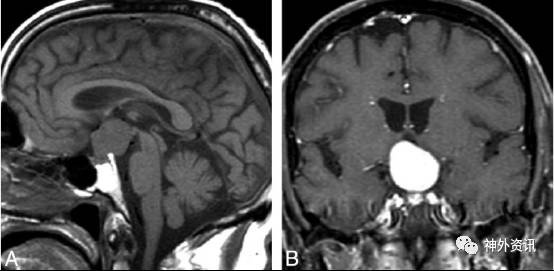

患者,女,26岁,因“ 头部外伤后发现颅内占位 40天 ”入院。患者40天前骑自行车与汽车相撞后倒地致头部出血,当时意识不清,家属诉约30分钟后自行苏醒,伴逆行性遗忘,左眼活动受限,视力无影响,也无肢体活动障碍等其他不适,至当地医院急诊,予“清创缝合及破伤风抗毒素”治疗后转来我院急诊。急诊头颅+眼眶CT显示:右侧额顶部头皮血肿、积气。同时见鞍上一占位性病变,建议MR复查(图1)”。遂以“颅底骨折,鞍上肿瘤”收住入院。

图1. CT 显示鞍上区等密度结节影,大小约 15.9×10.8mm,边界清,垂体柄显示不清。